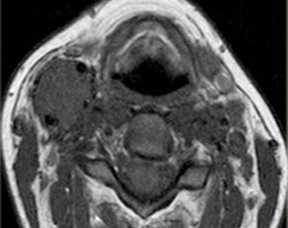

(Слева) УЗИ, поперечная проекция: визуализируется веретенообразная гипоэхогенная опухоль В и нижней трети шеи слева (известная локализация ПС). Обратите внимание на связь с корешками/ветвями ПС. На УЗИ в продольной плоскости (не показана) также определяется связь опухоли с плечевым сплетением - это подозрительный признак шванномы ПС.

(Справа) MPT (Т2 ВИ FS), аксиальная проекция: визуализируется шваннома ПС, связанная с корешком. УЗИ позволяет идентифицировать опухоль и отличить ее от лимфоузлов, чаще встречающихся в этой области. (Слева) УЗИ, поперечная проекция: визуализируется солидная гипоэхогенная опухоль с задним усилением, лежащая между передней и средней лестничными мышцами. Расположение в перивертебральном пространстве и УЗ-картина являются диагностическими признаками шванномы ПС.